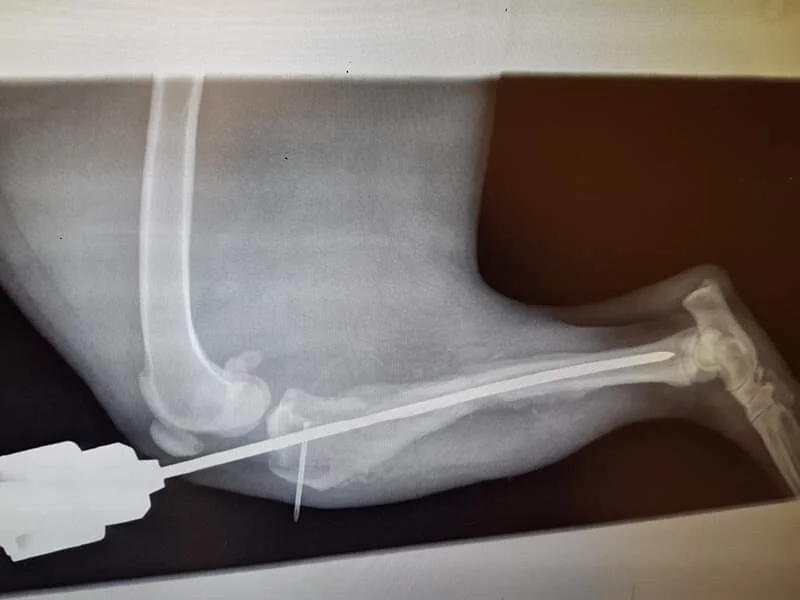

SAFE Perth works to save Suki's broken leg

Suki (pronounced Sookie) came into the care of SAFE Perth after flying from Broome on 16/12/19. Suki has a spiral fracture in her back left leg that is estimated to be 1-3 months old.

Due to the complexity of the fracture and the age of the injury, we are not yet sure which treatment path will work. We have started by trying to save the leg, at a cost of $2500. If this fails, Suki will need her leg amputated which will increase her vet bill even more.

At this time we are waiting to see how the pin helps her leg and hoping that amputation will not be required. If you can spare a few dollars to help with Suki's vet bills we would be really appreciative.